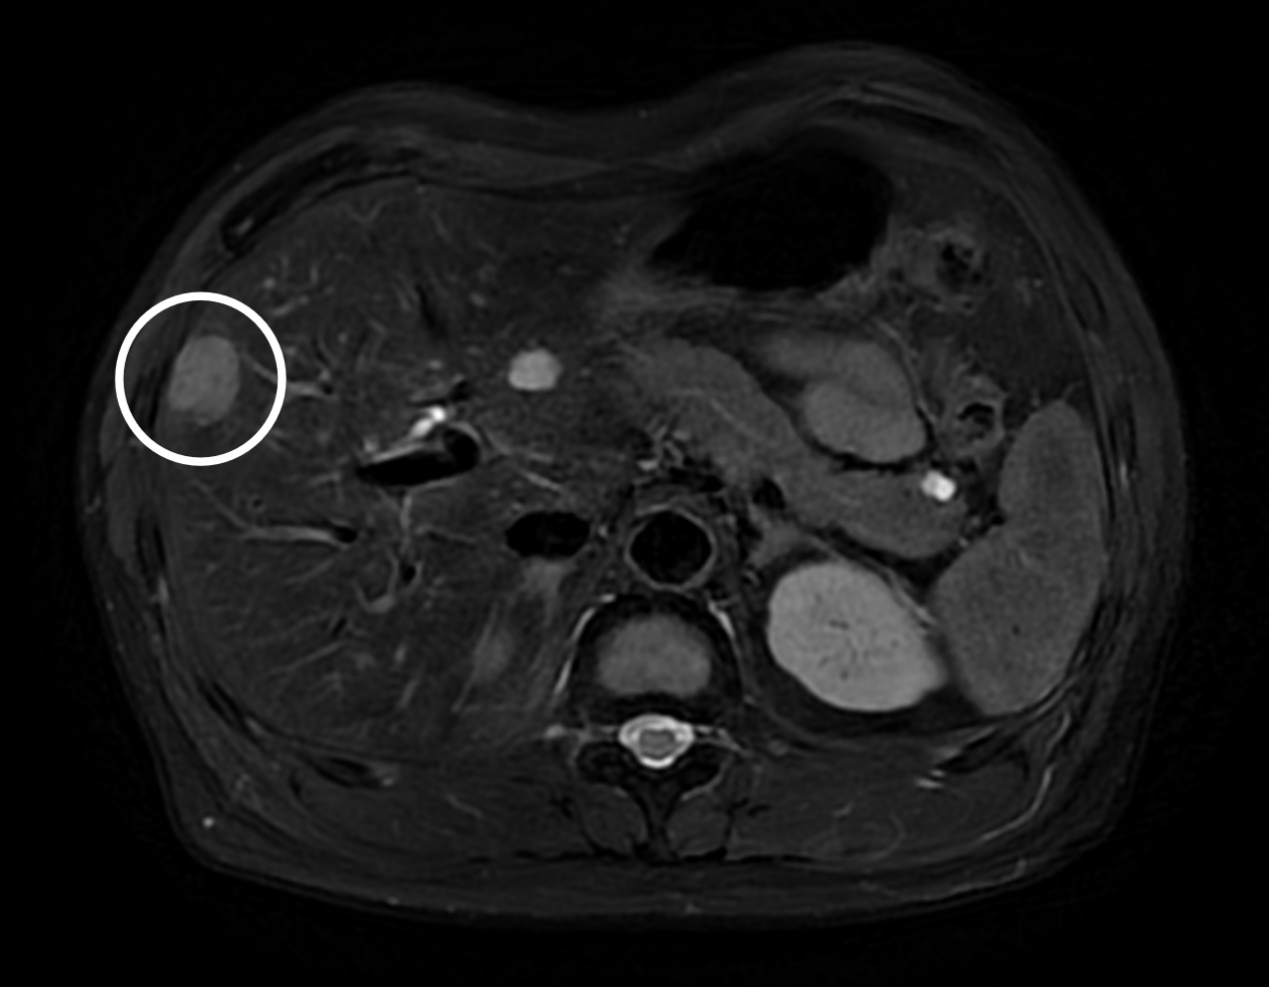

近日,上海市中医医院成功完成了首例腹腔镜肝肿瘤切除手术。患者刘先生(化名)今年45岁,患有多年的慢性乙型病毒性肝炎,一直进行治疗。近期复查时,发现在肝右前叶上段有一枚直径2厘米的异常区域,进一步超声造影检查显示,这块异常区域呈现出恶性肿瘤的“快进快出”特征,尽管刘先生还未出现腹痛腹胀等不适感,他还是听从超声科沈睿主任的建议立即前往该院外二科(肝胆外科)就诊。

外二科(肝胆外科)张敏峰主任接诊后,详细了解了患者病史,认为是肝癌的可能性非常大,建议他立即住院进一步检查,制定手术方案。虽然肝右叶叶上段属于比较困难的手术区域,但是,经过规范化术前评估,张敏峰主任团队还是一致认为有实施腹腔镜微创手术的条件。